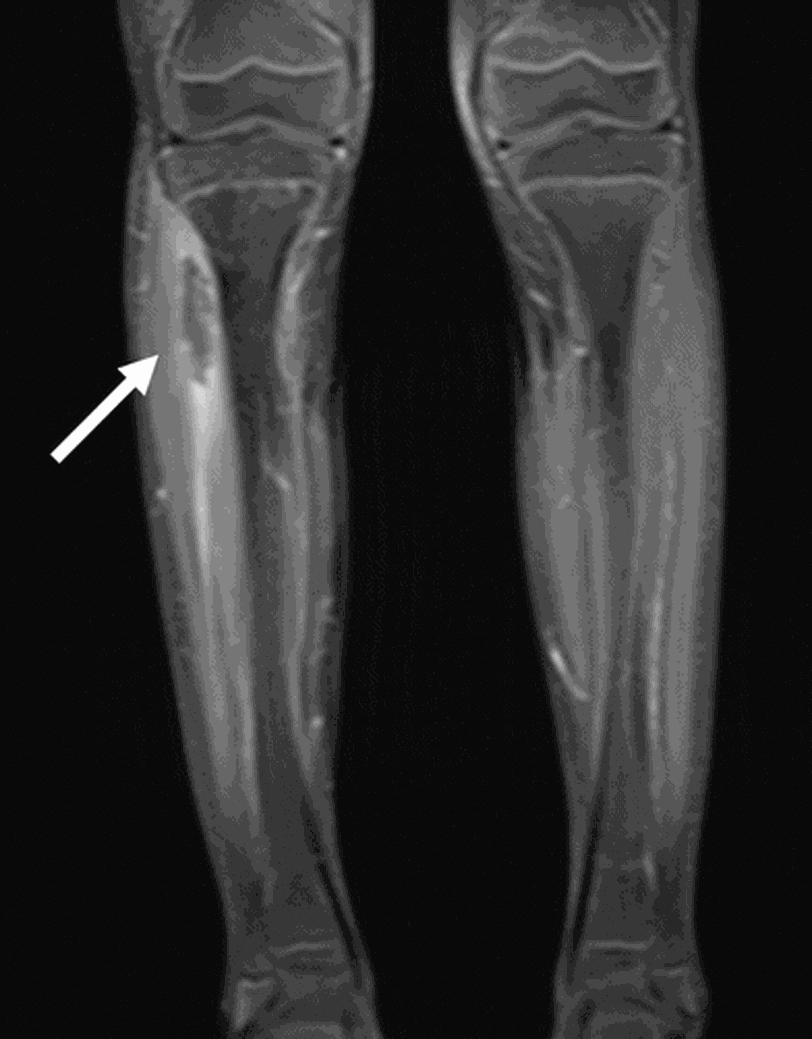

Osteomyelitis, the most common musculoskeletal infection in children, typically presents with pain and limp. There is a male preponderance due to increase microtraumas in males. Infection reaches the bone either by direct inoculation or hematogenous spread. In children, most commonly affected bone is femur. The signs and symptoms of acute osteomyelitis in children as pain, tenderness, erythema, fever, and refusal to walk. Involvement of bone is confirmed by radiological imaging and laboratory investigations. Both CRP and ESR are raised, however, theses findings are non-specific if they alone are considered. The gold standard diagnostic modality for acute osteomyelitis is MRI. The radiological imaging may be unremarkable; however, it is done in order to rule out other differential diagnosis like malignancy and fractures. The most common causative agent of acute osteomyelitis in children in Staphylococcus aureus. Other organisms may include Streptococcus agalactiae and Gram-negative bacteria for children below 2 months. Causative agents in 2-5 years age bracket are Streptococcus pyogenes and Streptococcus pneumoniae. Fungal agents that can cause osteomyelitis in immunocompromised children are Candida spp., Histoplasma spp., and Cryptococcus spp. Other pathogens may include Bartonella henselae and Mycobacterium tuberculosis. For infants less than 3 months of age, IV 3rd generation cephalosporin along with oxacillin are administered. For vaccinated children more than 3 months old, belonging to a community with prevalent MSSA, first generation cephalosporin such as cefazolin and oxacillin are started empirically. For unvaccinated children more than 3 months of age, the drug of choice is ceftriaxone and oxacillin. Source Acute infectious osteomyelitis in children: new treatment strategies for an old enemy https://link.springer.com/article/10.1007/s12519-020-00359-z Image via https://pubs.rsna.org/doi/full/10.1148/radiol.2017151929